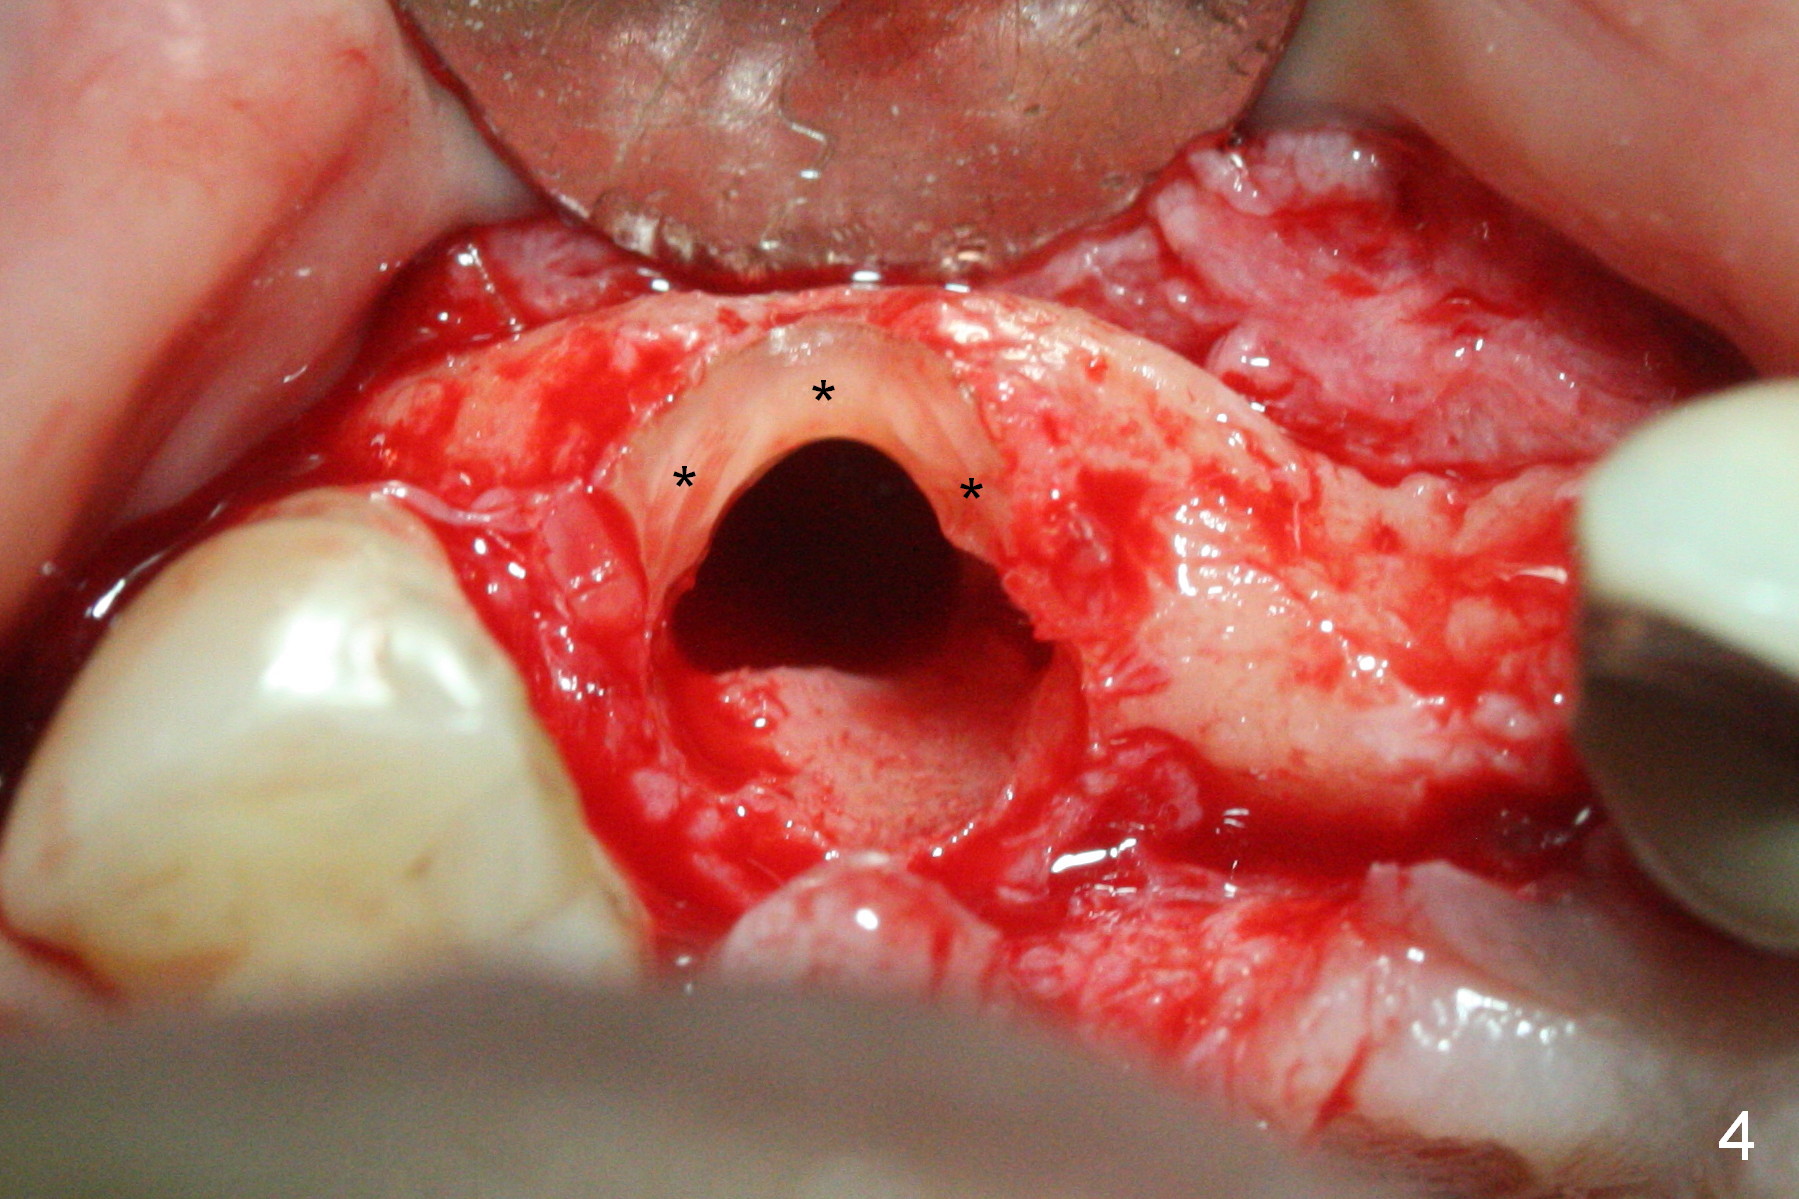

When the bridge is sectioned between #7 and 8, the tooth #6 is found non-salvageable (Fig.1).  Incision shows the atrophic buccal plate at #7 (Fig.2 arrowheads); to prevent the same feature from happening at #6 with thin buccal plate, the most buccal portion of the root is preserved (socket shield (Fig.2-4: *)).  The initial osteotomy is established in the palatal slope at #6 (Fig.5 circle) with 1.5 mm drill (Fig.6,7).  A portion of the root is visible in Fig.6 (arrowheads).  After sequential osteotomy with 2 mm, 3 mm (Fig.8) and 3.2 mm drills, a 4x15 mm implant is placed (Fig.10).  To accommodate the cross bite, the coronal portion of the implant (Fig.9 white circle) is positioned close to the socket shield.  It appears that the shield prevents the implant from encroaching the buccal plate.